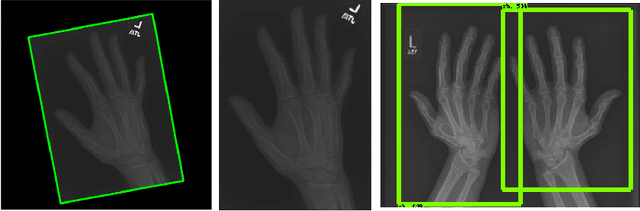

Abstract:Obtaining labels for medical (image) data requires scarce and expensive experts. Moreover, due to ambiguous symptoms, single images rarely suffice to correctly diagnose a medical condition. Instead, it often requires to take additional background information such as the patient's medical history or test results into account. Hence, instead of focusing on uninterpretable black-box systems delivering an uncertain final diagnosis in an end-to-end-fashion, we investigate how unsupervised methods trained on images without anomalies can be used to assist doctors in evaluating X-ray images of hands. Our method increases the efficiency of making a diagnosis and reduces the risk of missing important regions. Therefore, we adopt state-of-the-art approaches for unsupervised learning to detect anomalies and show how the outputs of these methods can be explained. To reduce the effect of noise, which often can be mistaken for an anomaly, we introduce a powerful preprocessing pipeline. We provide an extensive evaluation of different approaches and demonstrate empirically that even without labels it is possible to achieve satisfying results on a real-world dataset of X-ray images of hands. We also evaluate the importance of preprocessing and one of our main findings is that without it, most of our approaches perform not better than random. To foster reproducibility and accelerate research we make our code publicly available at https://github.com/Valentyn1997/xray